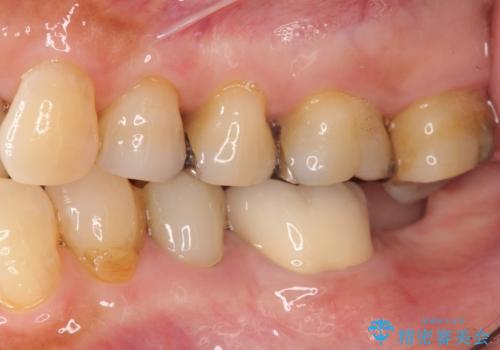

親知らずの移植 4年半経過症例 70代女性

- 親知らずの移植治療から4年半経過した患者様です。

他の歯の治療をご希望され、数年ぶりに来院して下さいました。

移植した親知らずは全く問題ないそうで、「まるで自分の歯のようです。本当にすごい技術ですね。」とおっしゃって下さいました。

歯肉の腫脹や退縮、動揺も認められませんでした。